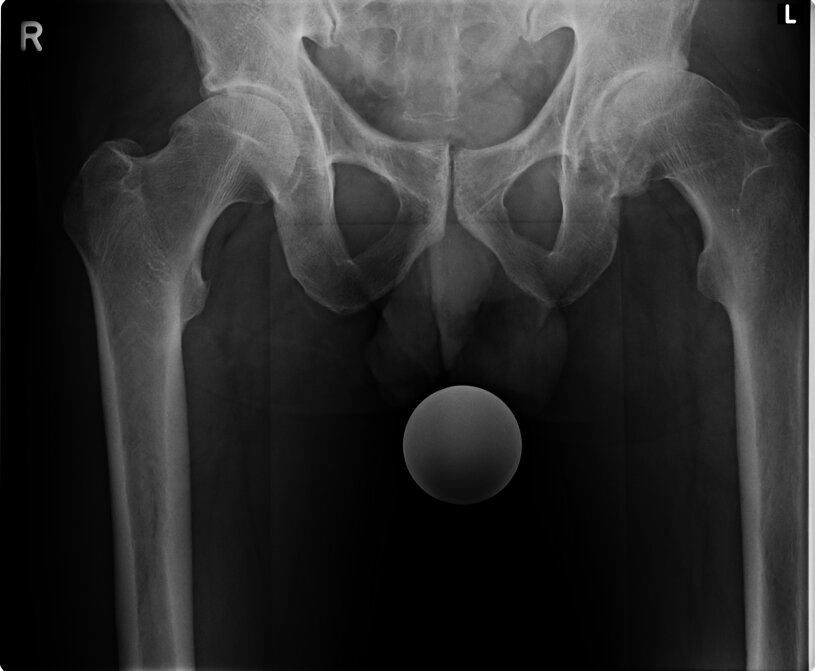

1.1

Aufnahme zeigt eine Verdrehung der linken Seite, anhand der Beckenlöcher.

Zudem muss das Becken seitlich verschoben sein.

Sichtbar anhand der Beinstellungen und der Verdrehung des Schenkelhalses.

Weiter wird ersichtlich, dass links das Becken hochgedrückt wird.

Eindeutig am Beckenspalt zu erkennen, das der Oberkörper nach links ausweicht und somit das Becken in der Höhe verzieht.

Auch drückt es oberhalb der Hüftkugel rechts das Becken über den Zug der seitlichen Oberkörper Haltung hoch und verzieht das Becken.